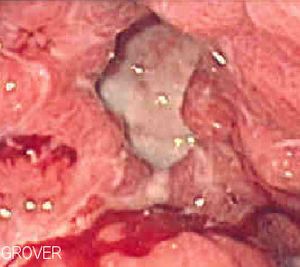

وقد أصبح بالإمكان حديثاً علاج معظم المضاعفات تنظيرياً، مثل وضع مشابيك (كليبسات) agraffe معدنية على الوعاء النازف عبر المنظار الضوئي أو حقن مواد مصلِّبة تغلق الوعاء النازف. وكذلك يمكن إجراء توسيع للبواب المسدود بوساطة بالون خاص عبر المنظار أيضاً. وعلى الرغم من أنه أصبح من النادر إحالة مريض قرحة العفج إلى الجراحة، إلا أنه لا يمكن الاستغناء عنها لعلاج معظم حالات الانثقاب.